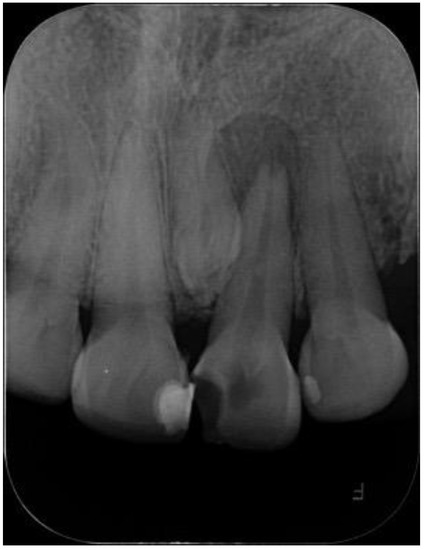

2.1. Case Report 1

| Case Report 1 | Male | Conoid mesiodens with dilaceration in close contact to tooth 2.1, horizontal position | 9 years old | Clinically, due to increased palatal volume | Tooth vestibuloversion 2.1 Palatal volume increase |